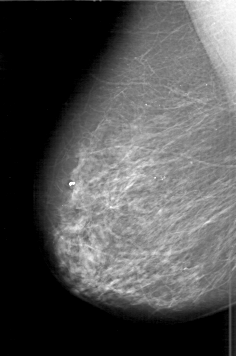

D_4198_1.RIGHT_MLO

RIGHT_CC LINES 6166 PIXELS_PER_LINE 4276 BITS_PER_PIXEL 12 RESOLUTION 43.5 NON_OVERLAY

RIGHT_MLO LINES 6046 PIXELS_PER_LINE 4006 BITS_PER_PIXEL 12 RESOLUTION 43.5 NON_OVERLAY